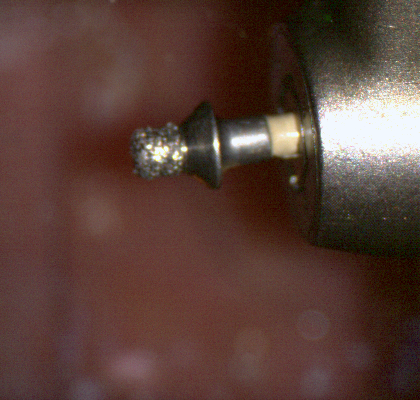

The following pictures depict the sequence of burs we recommend that you use to finish a preparation quickly. While patient is getting numb, take a quick look at the clearance you will need to reach proper material thickness. Once the quadrant is isolated with isolite and optragate, take an occlusal router bur and create a trough to gain the proper depth. Follow that with a flat disk, and you can quickly reduce the occlusal height.

A shoulder bur of .8 mm thickness can help you reduce the interproximal areas as well as the buccal and lingual margin lines. Before finishing the prep, place hemostatic agent like expasyl in the sulcus and place retraction cord. while it is setting, check your reduction. If you need more space, now is the time to reduce some more.